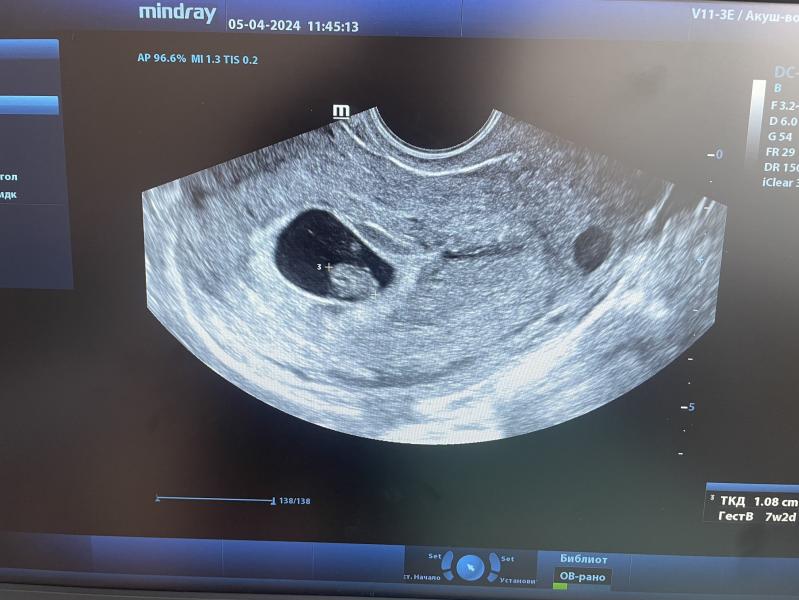

Моя крошка🥹🥹🥹

Увидела сегодня и 💓 услышала. Когда сб услышала заплакала)